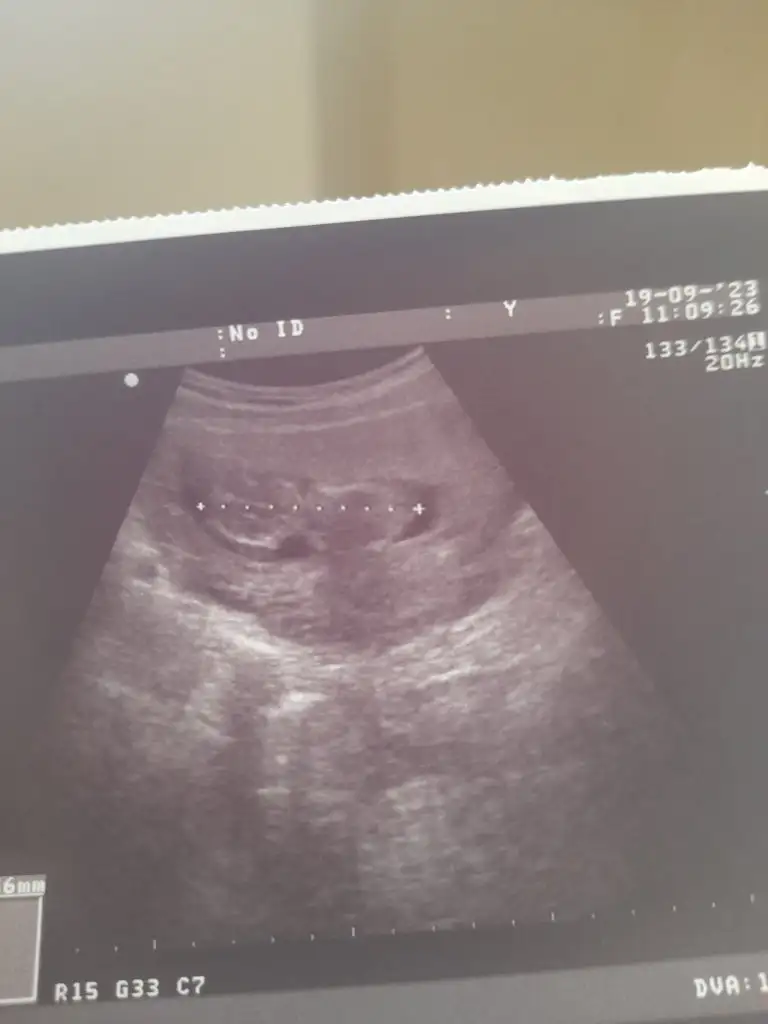

Dünkü ultrason fotografimiz